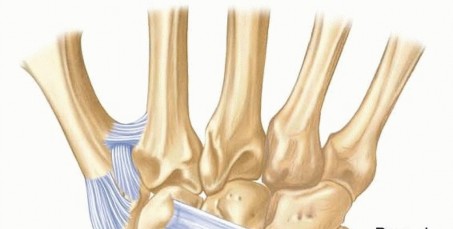

To master carpal fracture fixation, one must first possess an encyclopedic knowledge of carpal anatomy and its dynamic biomechanics. The carpus is an evolutionary marvel of engineering, a complex, intercalated array of eight bones forming two distinct rows, each possessing multiple, highly congruent articular surfaces. The proximal row (scaphoid, lunate, triquetrum) functions as an intercalated segment, lacking any direct tendon insertions. Its movement is entirely dictated by mechanical forces exerted by the surrounding articular contours and the robust intrinsic and extrinsic ligamentous networks. Disruption of any single component within this delicate balance inevitably leads to profound kinematic derangement, asynchronous joint loading, and rapid, progressive cartilaginous degradation.

The capitate, acting as the keystone of the distal carpal row and the primary axis of wrist rotation, warrants specific anatomical focus. It articulates with seven surrounding bones, making its geometric restoration paramount. Crucially, the vascular anatomy of the capitate mirrors the precarious nature of the scaphoid. The predominant blood supply enters the distal half of the bone via palmar vessels and flows retrograde toward the proximal pole (the head). Consequently, a fracture through the capitate neck physically severs this intraosseous vascular network, placing the proximal articular fragment at an exceptionally high risk for avascular necrosis (AVN). This anatomical reality dictates that capitate neck fractures must be treated with the utmost urgency and rigid fixation to optimize the potential for revascularization.

The hamate presents its own unique anatomical complexities, primarily divided into the body and the hook (hamulus). The hamate hook is a slender, volar-projecting osseous prominence that serves as a critical biomechanical pulley for the ulnar flexor tendons of the digits. Furthermore, it acts as the ulnar attachment site for the transverse carpal ligament (forming the roof of the carpal tunnel) and the pisohamate ligament. The hook also forms the radial border of Guyon's canal, intimately associating it with the ulnar nerve and artery. Fractures of the hook, often sustained during racquet sports or golf, not only disrupt this pulley mechanism but also pose a direct mechanical threat to the adjacent ulnar neurovascular bundle, potentially leading to acute neuropathy or vascular thrombosis.

The trapezium and triquetrum similarly possess specialized anatomical features that dictate their fracture patterns and surgical management. The trapezium features a prominent volar ridge, which, akin to the hamate hook, serves as the radial attachment for the transverse carpal ligament. Medial to this ridge lies a deep fibro-osseous groove that houses the flexor carpi radialis (FCR) tendon. Fractures of the trapezial ridge can lead to painful FCR tendinopathy or rupture. The triquetrum, situated on the ulnar aspect of the proximal row, is heavily tethered by the dorsal radiocarpal and dorsal intercarpal ligaments. Extreme wrist flexion and ulnar deviation can cause these robust ligaments to avulse a fragment of the dorsal triquetral cortex, resulting in the most common non-scaphoid carpal fracture. Understanding these specific ligamentous and tendinous associations is critical for interpreting fracture displacement and planning surgical approaches.